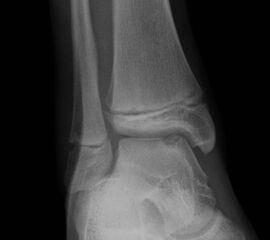

Fugengelenkfrakturen treten typischerweise vor dem 10. Lebensjahr auf, in einer Phase, in welcher die Wachstumsfugen noch weit offen sind. Dieser Frakturtyp betrifft fast ausschließlich den medialen Malleolus. Laterale Frakturen sind extrem selten, teilweise kommt es zu lateralen Bandverletzungen oder Fugenschaftfrakturen der distalen Fibula. Die Frakturlinie verläuft in einer Verlängerungslinie von der medialen Taluskante nach proximal. Häufig stellen sich Verletzungen des Innenknöchels im Röntgenbild schlechter dar, insbesondere wenn die Aufnahmen verdreht sind oder die Ebene der Fraktur bei geringer Dislokation verkippt zur Röntgenebene liegt. Besteht klinisch der geringste Hinweis auf eine Verletzung des Innenknöchels, muss aufgrund der Tragweite der Verletzung durch entsprechende Aufnahmen gegebenenfalls auch Schnittbildverfahren die Verletzung sicher diagnostiziert oder ausgeschlossen werden (Abb. 15).